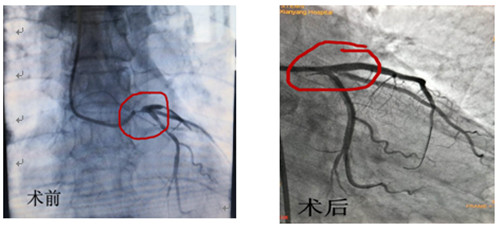

術(shù)前術(shù)后造影對(duì)比

12月16日早上8點(diǎn)30分手術(shù)如期進(jìn)行,術(shù)前IVUS評(píng)估:左主干自口部至末端彌漫狹窄,最小管腔面積<1mm2,斑塊負(fù)荷程度>90%,主要為纖維脂質(zhì)斑塊,無(wú)明顯鈣化,回旋支開口尚可,前降支近段主要為纖維脂質(zhì)斑塊,亦無(wú)明顯鈣化。據(jù)此,手術(shù)方案定為:前降支近段至左主干口部串聯(lián)植入2枚支架,回旋支近段1枚支架,無(wú)需旋磨、切割,支架植入后IVUS評(píng)估:支架膨脹、貼壁良好,左主干口部支架梁覆蓋完全,手術(shù)完美收官。此系心內(nèi)二病區(qū)左梅主任及其團(tuán)隊(duì)在導(dǎo)管室配合下完成的我院首例自主IVUS指導(dǎo)下左主干PCI。